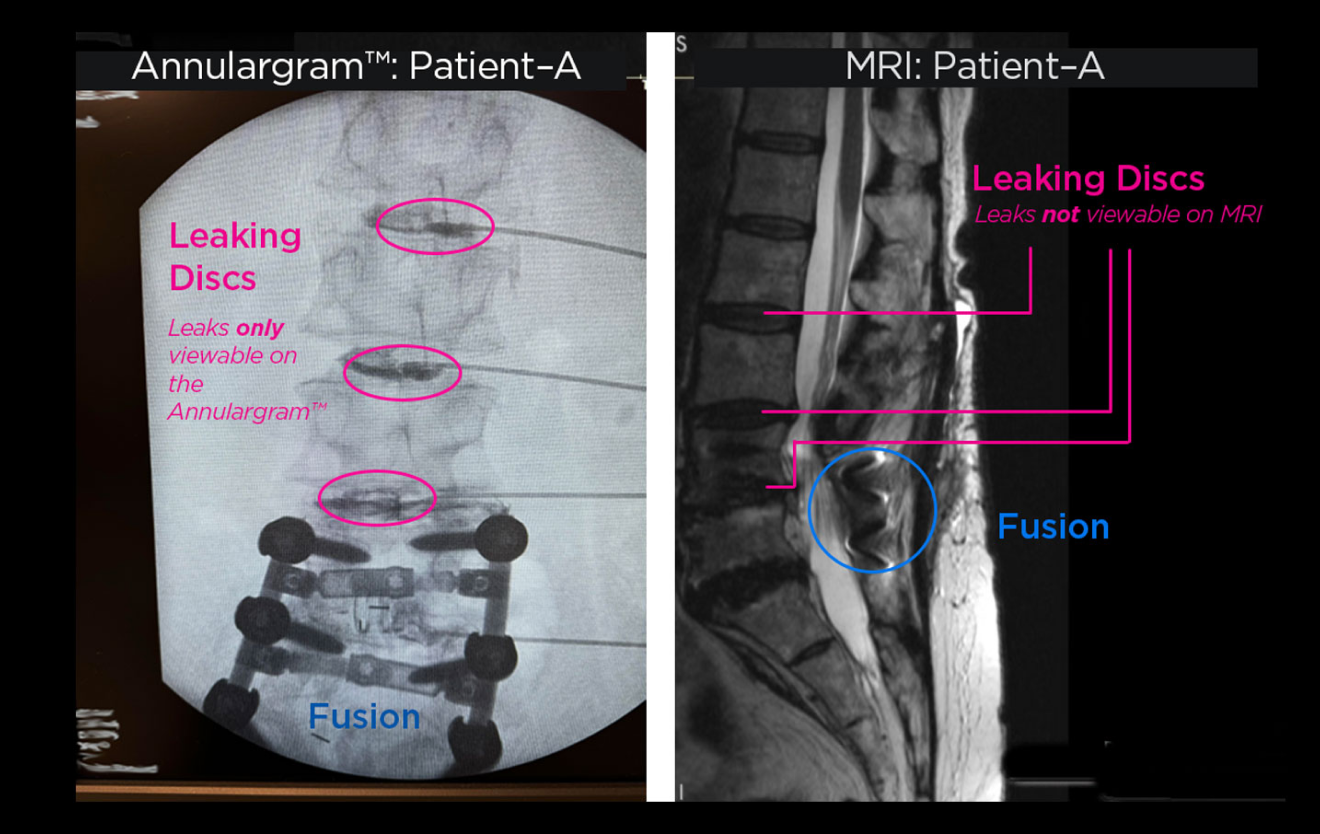

The Annulargram™ and MRI comparison

Lumbar Spine with fusion and leaking discs.

Annulargram™

We test every disc in the region to identify even the most subtle disc tears. This allows us to be proactive, addressing small tears before they lead to large herniations or degeneration. The Annulargram is so important that its a necessary part of the DISCSEEL Procedure.

During your Annulargram, X-ray contrast is mixed with a little antibiotic, and is injected into the outer annulus fibrosus of your disc to identify subtle disc tears. Next, Fibrin is injected into each tear to immediately seal the disc. Over the following months, the Fibrin promotes disc tissue growth, sealing and healing previously torn discs.